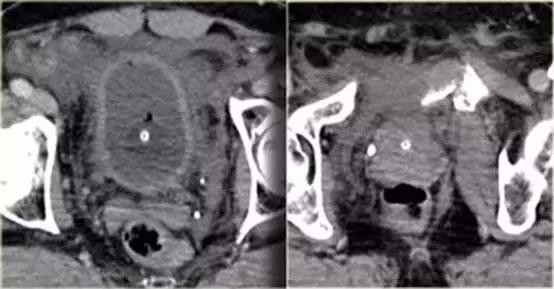

同一病人的CT常规增强检查

结果

有一个指向膀胱的骨盆骨折碎片。

膀胱直肠隐窝积液。

膀胱造影前后CT对比图像

膀胱中导尿管有对比剂, 膀胱直肠隐窝中也有渗出的对比剂。

‘磨牙征’ 提示腹膜外膀胱破裂。